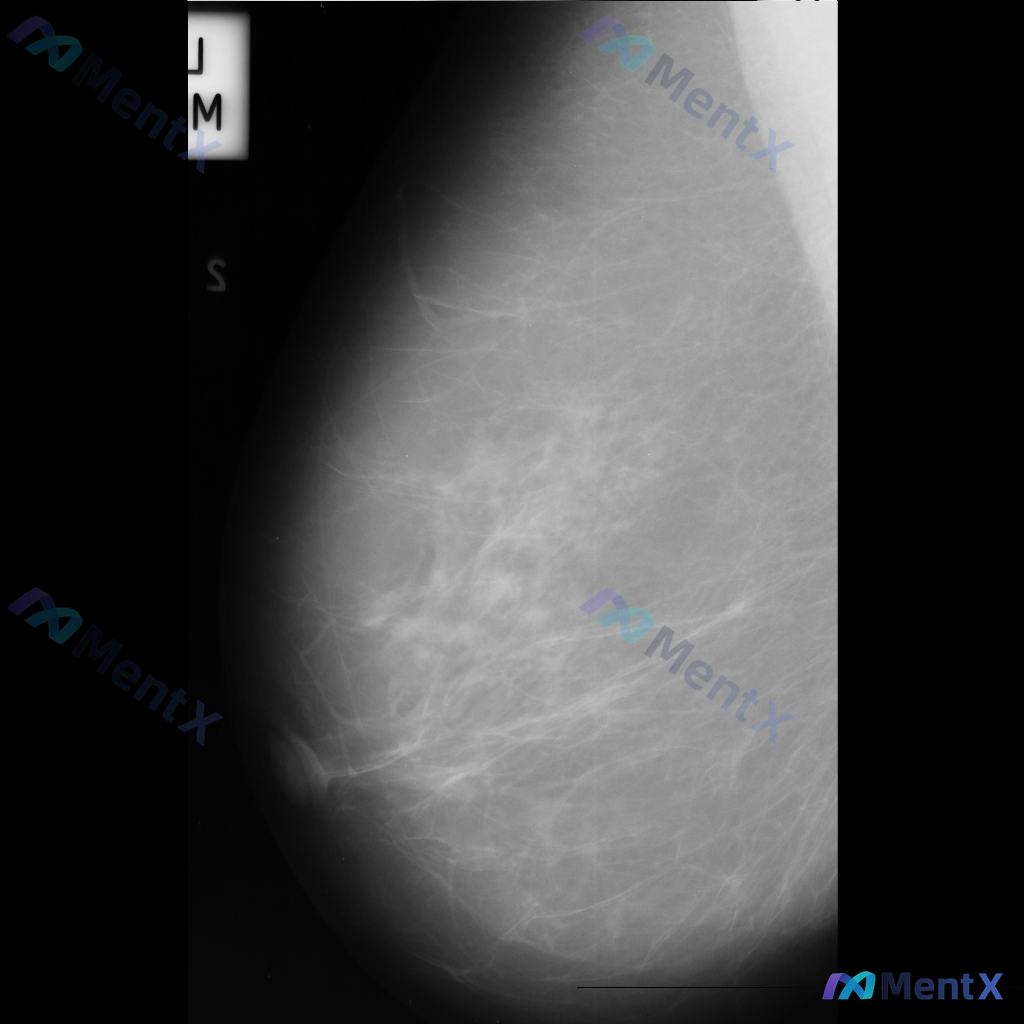

整理到一张乳腺钼靶影像的读片资料,想和大家讨论一下读片思路: 影像里能看到的主要异常是乳腺内结构扭曲(正常导管小叶结构有集中、牵拉、不规则向中心汇聚的表现,但没有明确肿块),同时还有不对称致密影(局部组织密度增高,和周围或对侧分布不太一致)。另外,乳腺本身纤维腺体组织偏多,可能属于 BI-RADS...

整理到一份乳腺钼靶的影像讨论资料,背景是不均匀致密型乳腺(BI-RADS C类),主要发现是一处不对称致密影——目前描述里没有提到明确的肿块、簇状微钙化或结构扭曲这类典型征象。 想跟大家讨论一下: 1. 单看这组表现,你第一反应会先往哪个方向考虑? 2. 这种情况下,你觉得最需要优先补充的评估是什么...